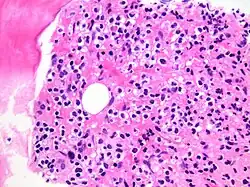

Immune Infiltration

This occurs when immune cells like lymphocytes and macrophages migrate into tissues in response to infection, injury, or inflammation, aiding in defense and healing but potentially contributing to autoimmune diseases if misdirected.[1] Immune cells (especially lymphocytes) also infiltrate into malignant tumors and other neoplasms.[2]